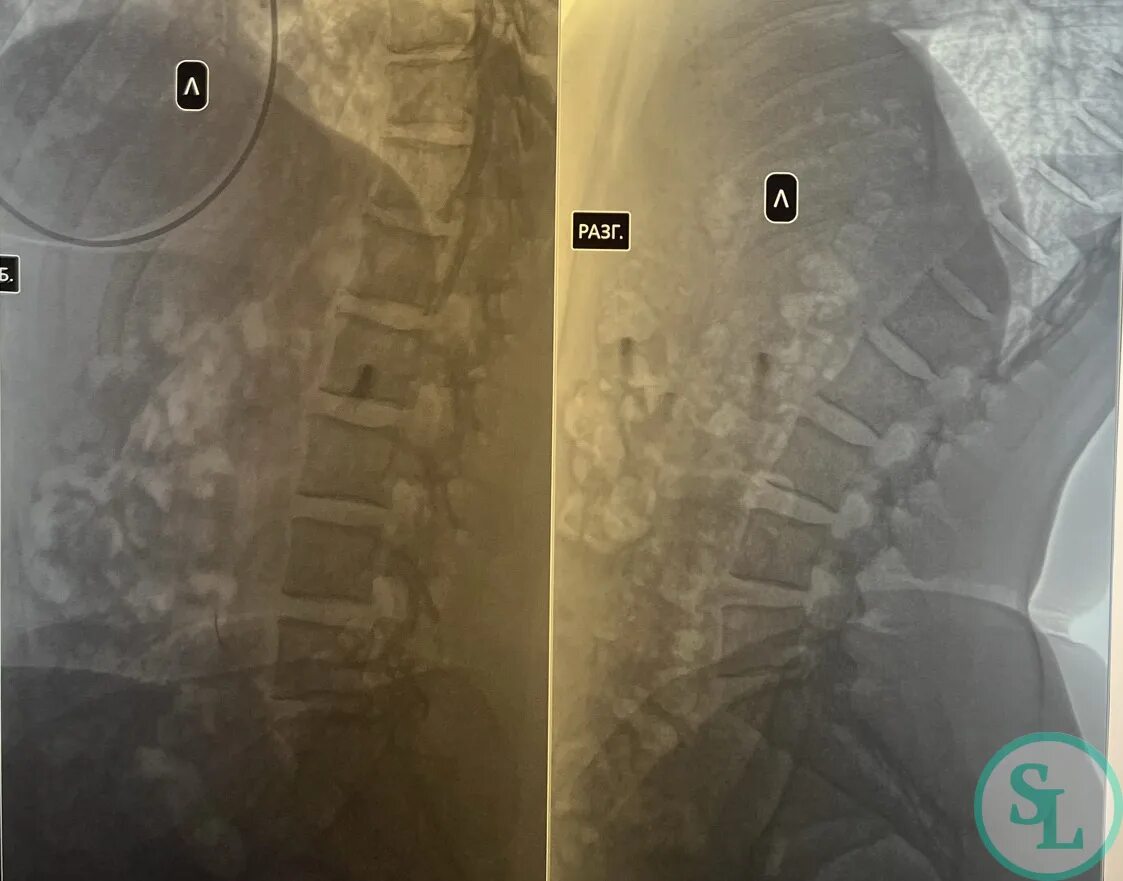

Грыжа диска на уровне l5 s1